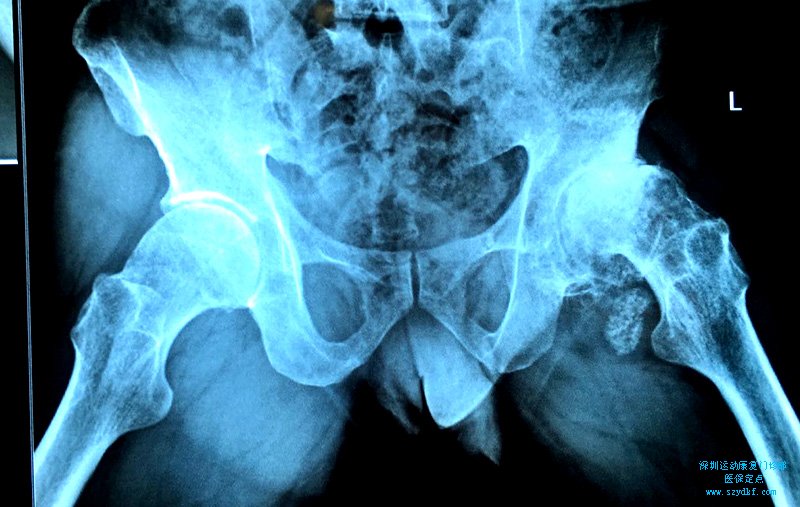

左侧股骨头坏死

王某某 男 47岁 主诉:左髋部疼痛不适伴活动受限半年余。 现病史:患者自诉半...